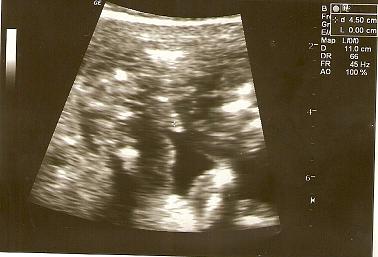

ja widzę chłopca , ale nie jestem pewna ;-)Zobacz załącznik 236421Dziewczyny a jak sądzicie jaka to płeć, lekarz nie był do końca pewny...Zobacz załącznik 236420

Zobacz załącznik 236421Dziewczyny a jak sądzicie jaka to płeć, lekarz nie był do końca pewny...Zobacz załącznik 236420

hehe, a u nas mniej wiecej tak wyglądała dziewczynka, wiec nie dziwie sie, ze lekarz nie byl pewny![]()